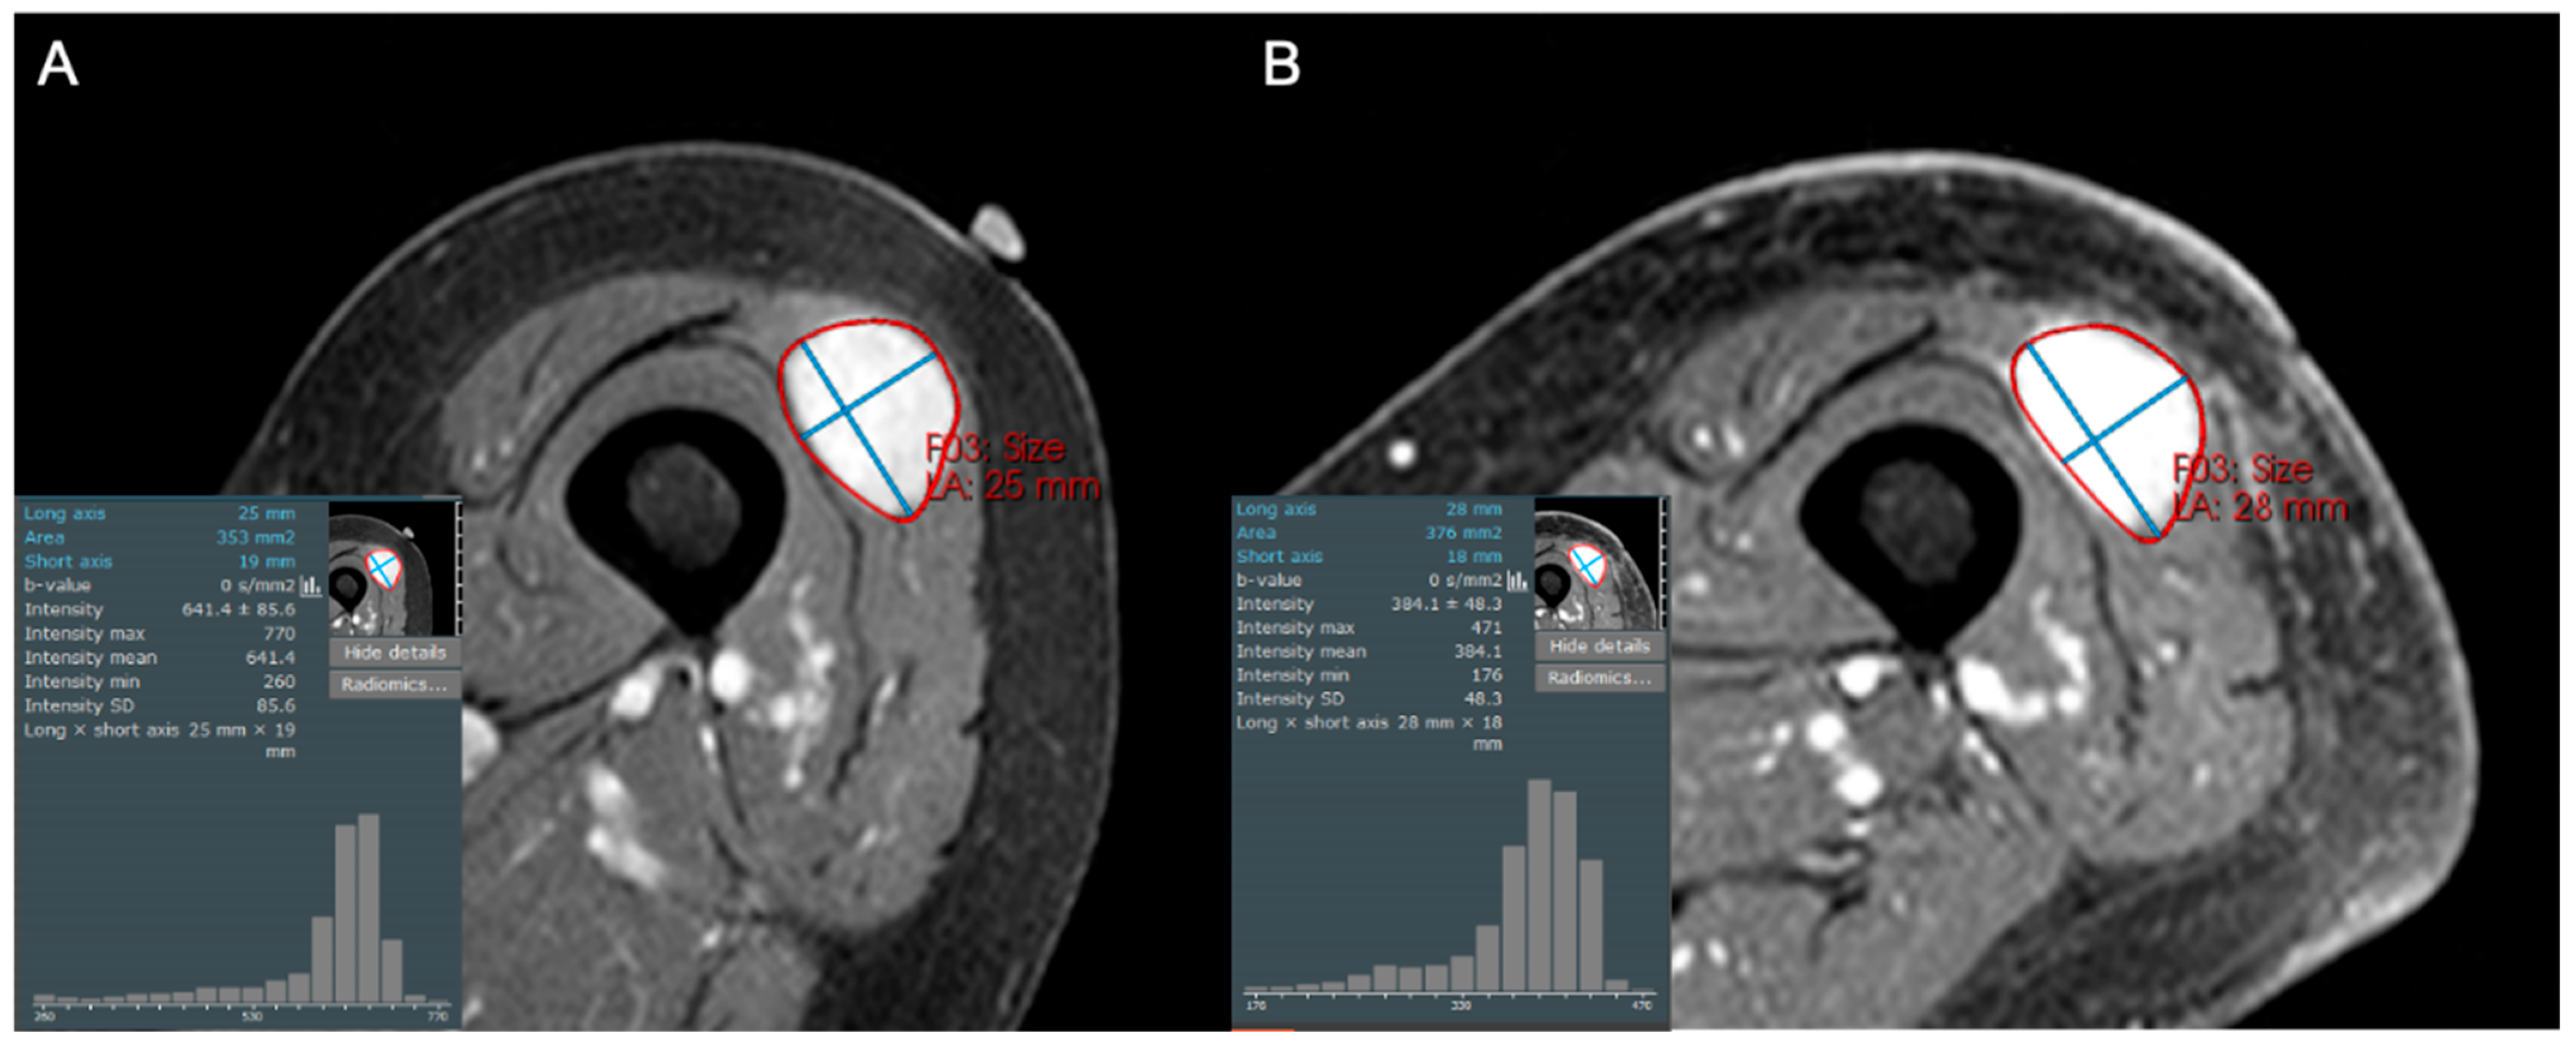

- Subhawong, T.K.; Feister, K.; Sweet, K.; Alperin, N.; Kwon, D.; Rosenberg, A.; Trent, J.; Wilky, B.A. MRI Volumetrics and Image Texture Analysis in Assessing Systemic Treatment Response in Extra-Abdominal Desmoid Fibromatosis. Radiol. Imaging Cancer 2021, 3, e210016. [Google Scholar] [CrossRef]

- Singer, A.D.; Pattany, P.M.; Fayad, L.M.; Tresley, J.; Subhawong, T.K. Volumetric segmentation of ADC maps and utility of standard deviation as measure of tumor heterogeneity in soft tissue tumors. Clin. Imaging 2016, 40, 386–391. [Google Scholar] [CrossRef]